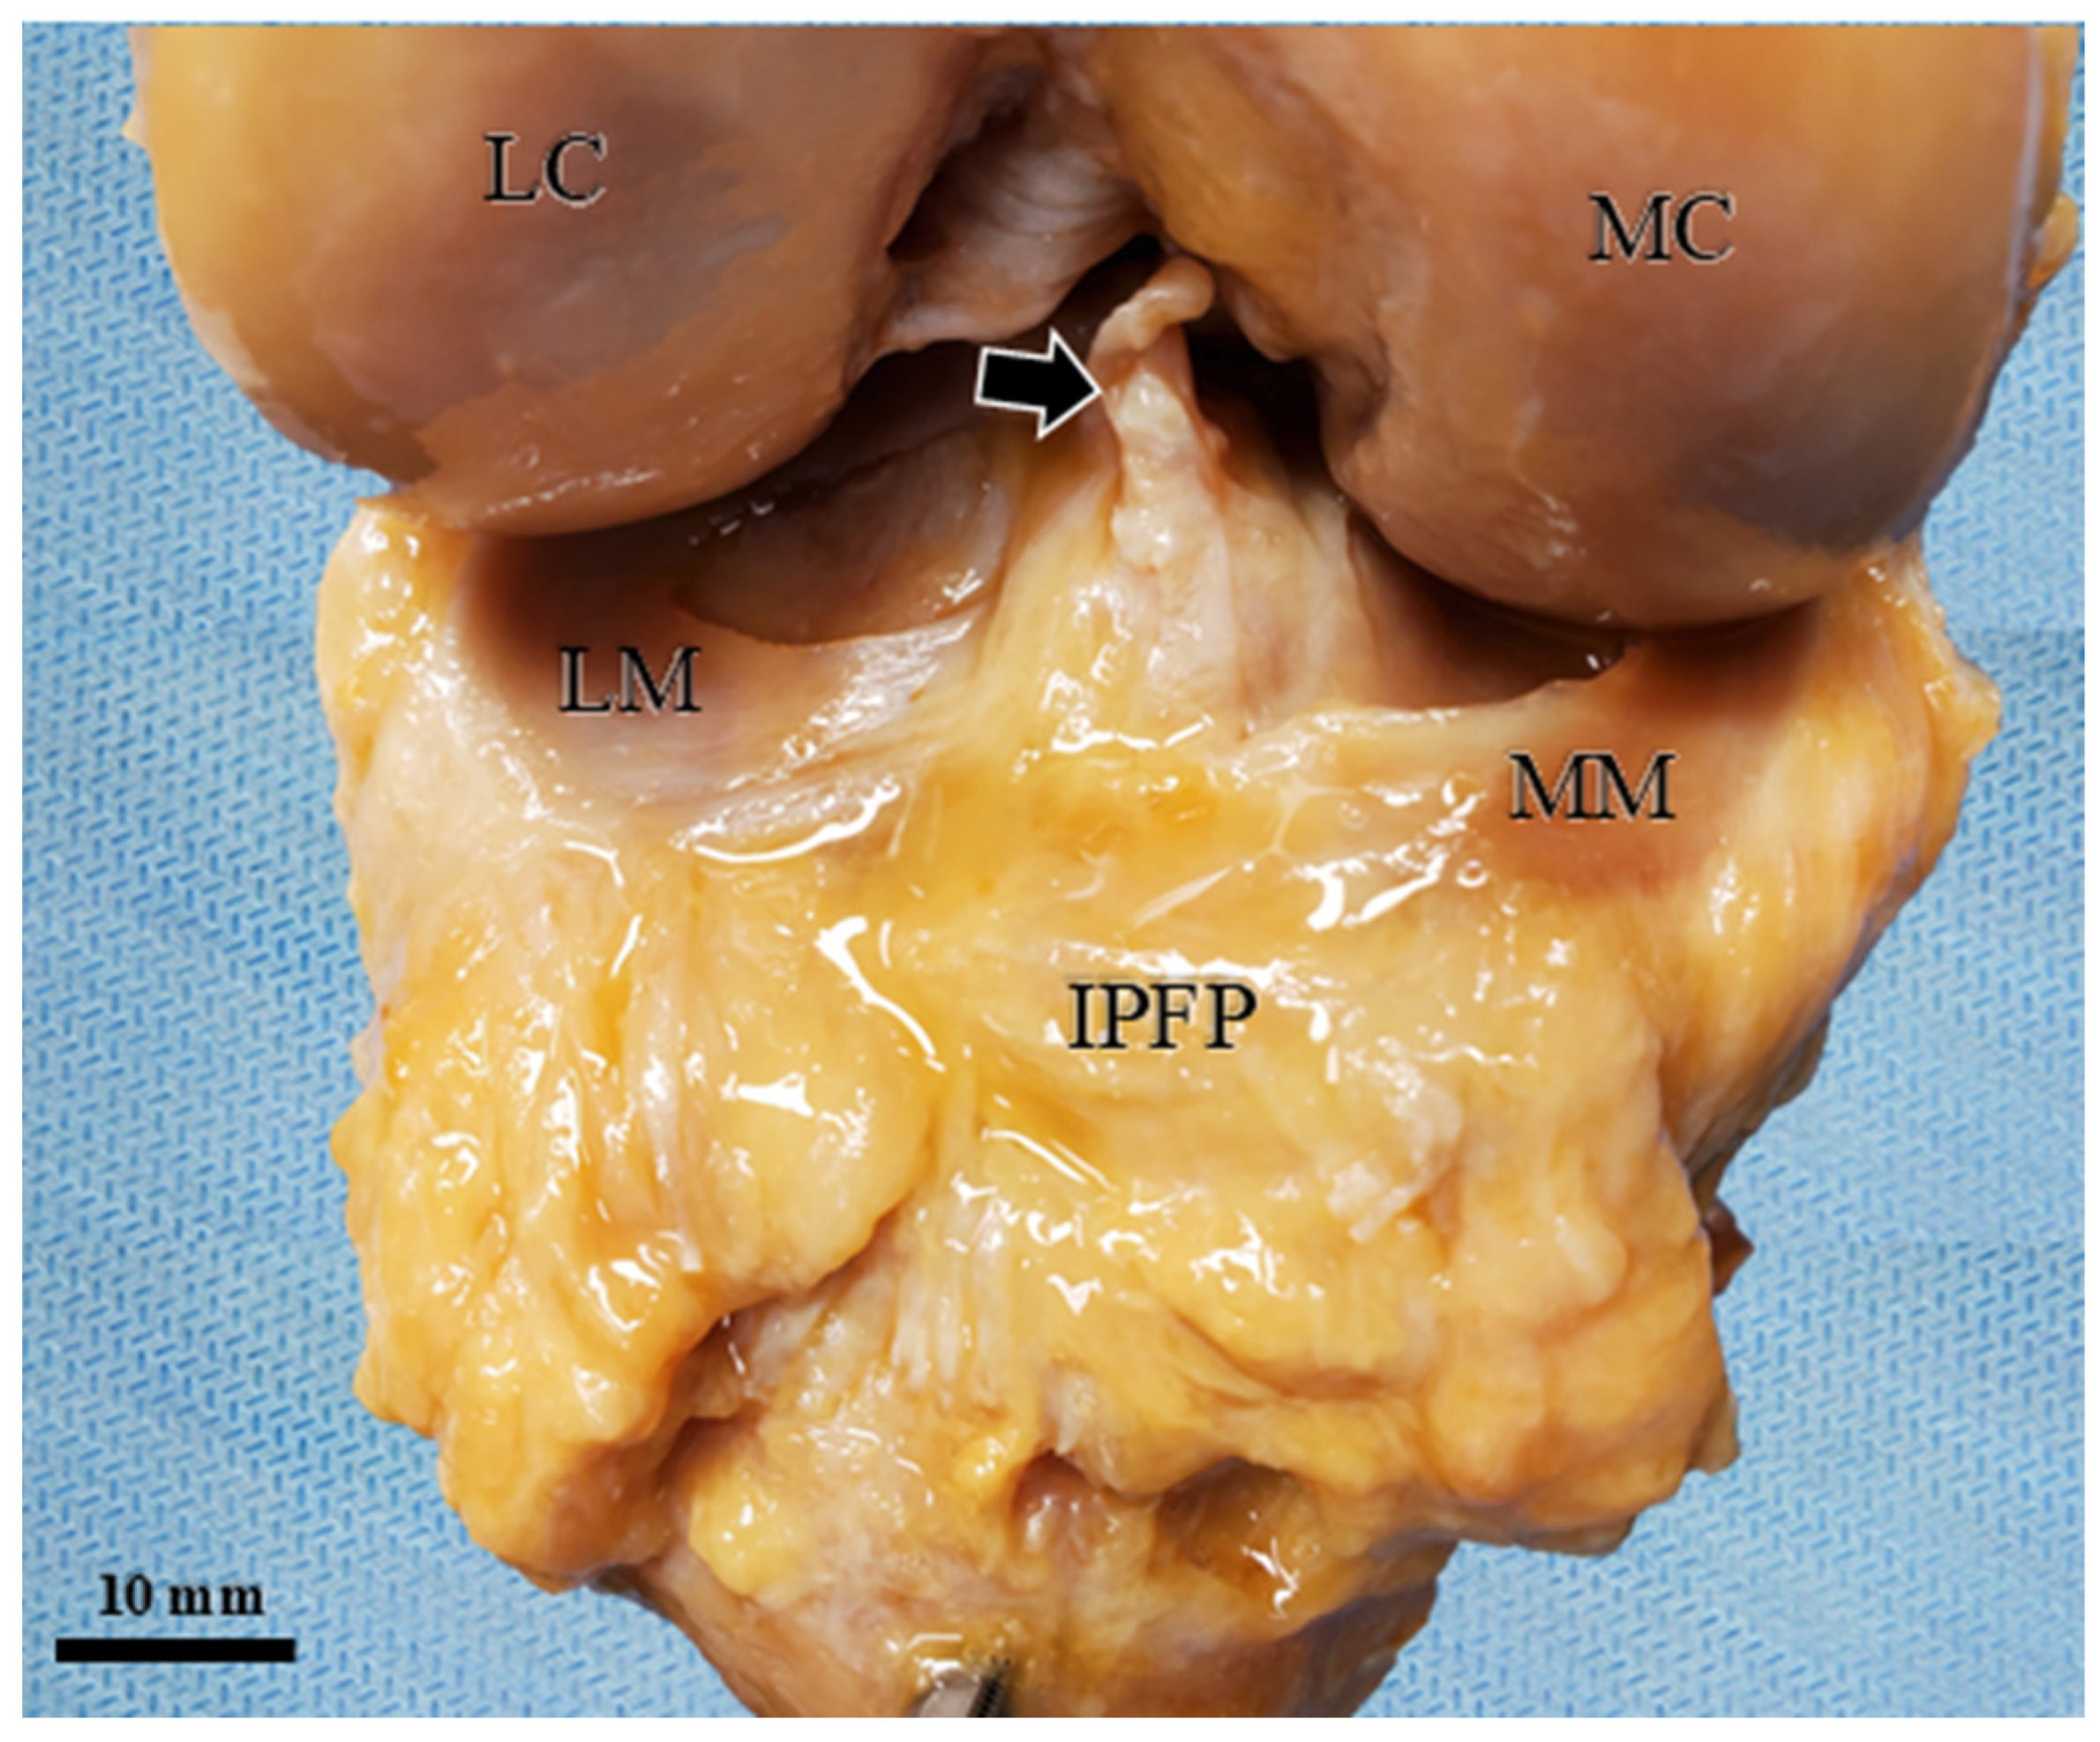

| Segment Abbreviation | Full Name | Macroscopic Anatomical Location | Histological and Structural Features |

|---|---|---|---|

| SPP-SEG | Superficial Proximal Segment | Connects the patella directly to the superficial layer of the patellar tendon. | Densely packed adipocytes. Separated from the SPD-SEG by connective tissue septa. |

| SPD-SEG | Superficial Distal Segment | Bounded by the patellar tendon, deep infrapatellar bursa, and tibia. | Adipocytes present. Linked to the tibia via the complex connective tissue of the joint capsule. |

| IPP-SEG | Infrapatellar Plica Segment | Regarded as the extended tissue of the infrapatellar plica (ligamentum mucosum). | High ratio of dense connective tissue mixed with adipocytes. Structurally less deformable. |

| DSV-SEG | Deep Synovial Segment | Deepest portion near the joint cavity. Separated from the patella by a horizontal cleft. | Characterized by a synovial cell lining on its articular surface. |

| AFC-SEG [Target Region] | Adipo-Follicular Segment | Bounded by SPD-SEG, IPP-SEG, and tibia. Connected to the anterior horns of the menisci. | Contains unique follicle-like spaces. Highly compliant and susceptible to joint pressure changes. |